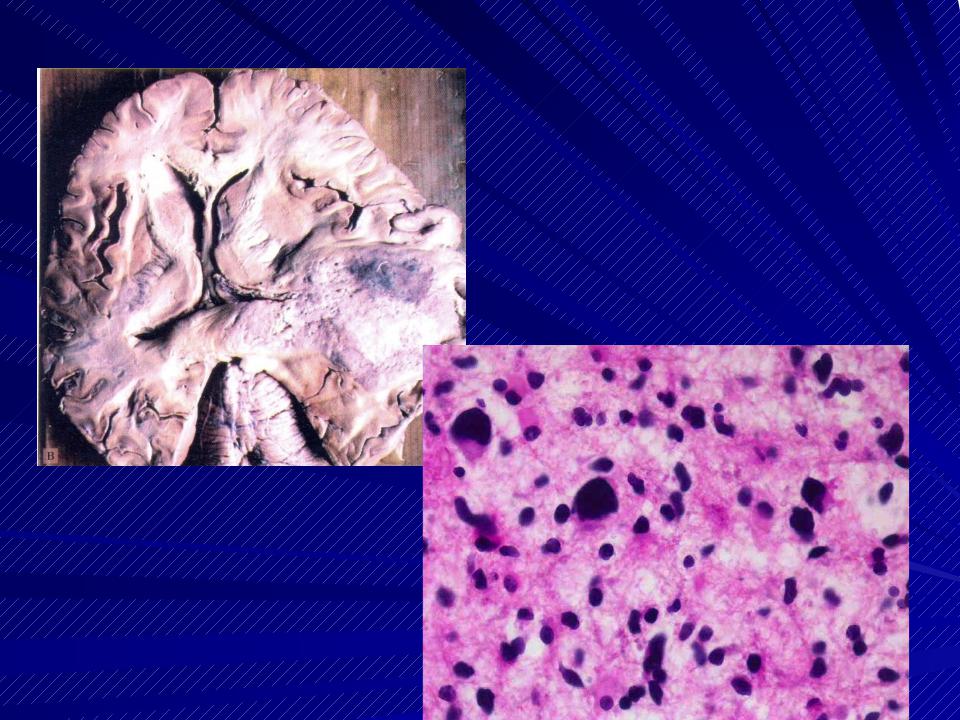

Микрофотографии гистологии глиобластомы головного мозга